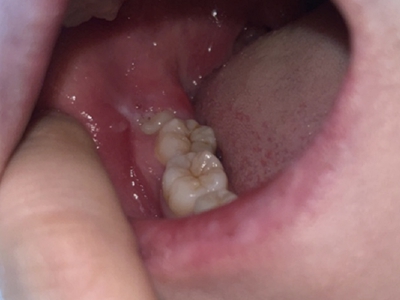

牙龈

红肿

智齿冠周炎智齿周围牙龈红肿图

智齿冠周炎表现为牙列尽头智齿阻生,一部分智齿未萌出,周围的牙龈红肿,空隙变大,并有食物残渣潴留,患者自觉病变位置疼痛,并伴有张口受限及咀嚼困难。